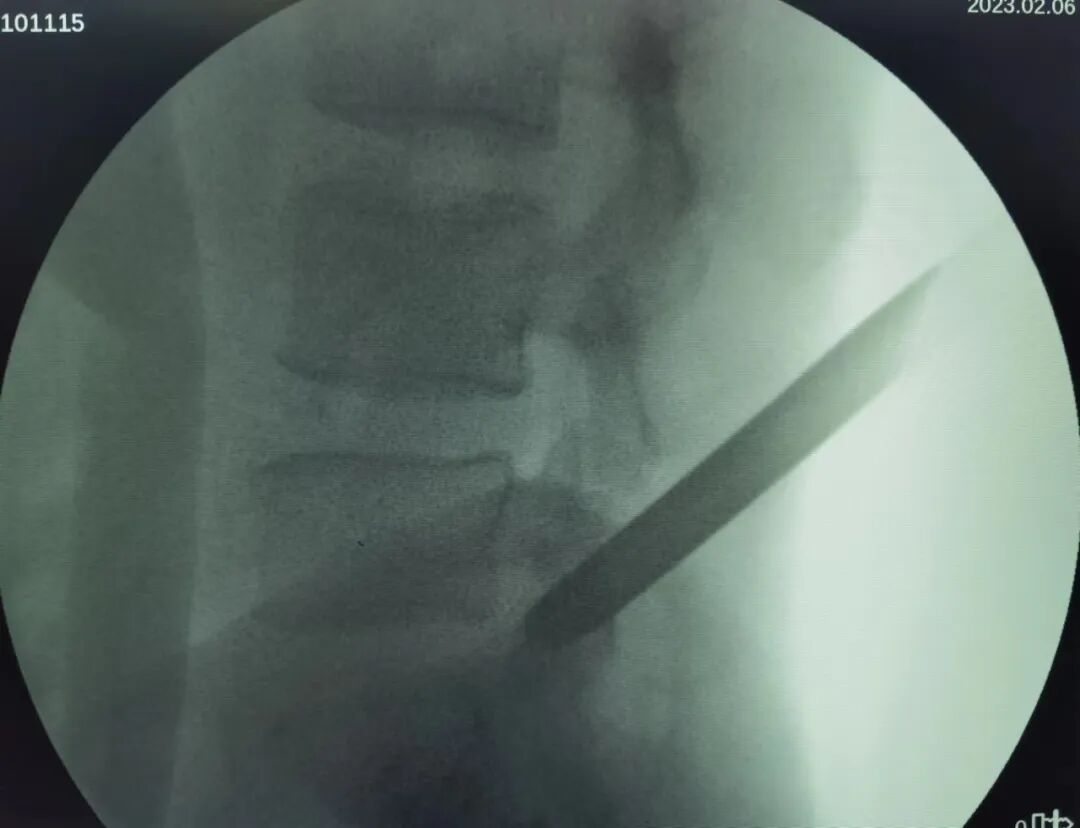

第三步:切开皮肤、置入导丝、扩张通道、建立手术通路

穿刺针尖到达上关节突后,正侧位透视位置难以,通过穿刺针置入导丝并移去穿刺针,置入克氏针确定位置,逐级扩张皮下及筋膜层至关节突外侧缘,随后置入环锯套筒行关节突成形建立手术通道。

开刀孔怎么开刀椎间孔镜手术技术,不开刀解决腰腿疼痛_https://www.jmylbn.com_新闻资讯_第12张

开刀孔怎么开刀椎间孔镜手术技术,不开刀解决腰腿疼痛_https://www.jmylbn.com_新闻资讯_第13张

以环锯及扩张套管于L5/S1节段将手术入路逐级扩大成形